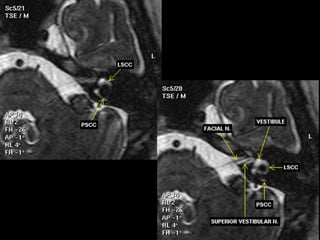

 The images are shown from a left temporal bone,

from

 cranially to caudally. All images have a 0.7 mm

slice

 thickness.

T1

 Axial T1-weighted MR Images

 The images are shown from a right temporal

bone, from

 cranially to caudally. All images have a 3.0 mm